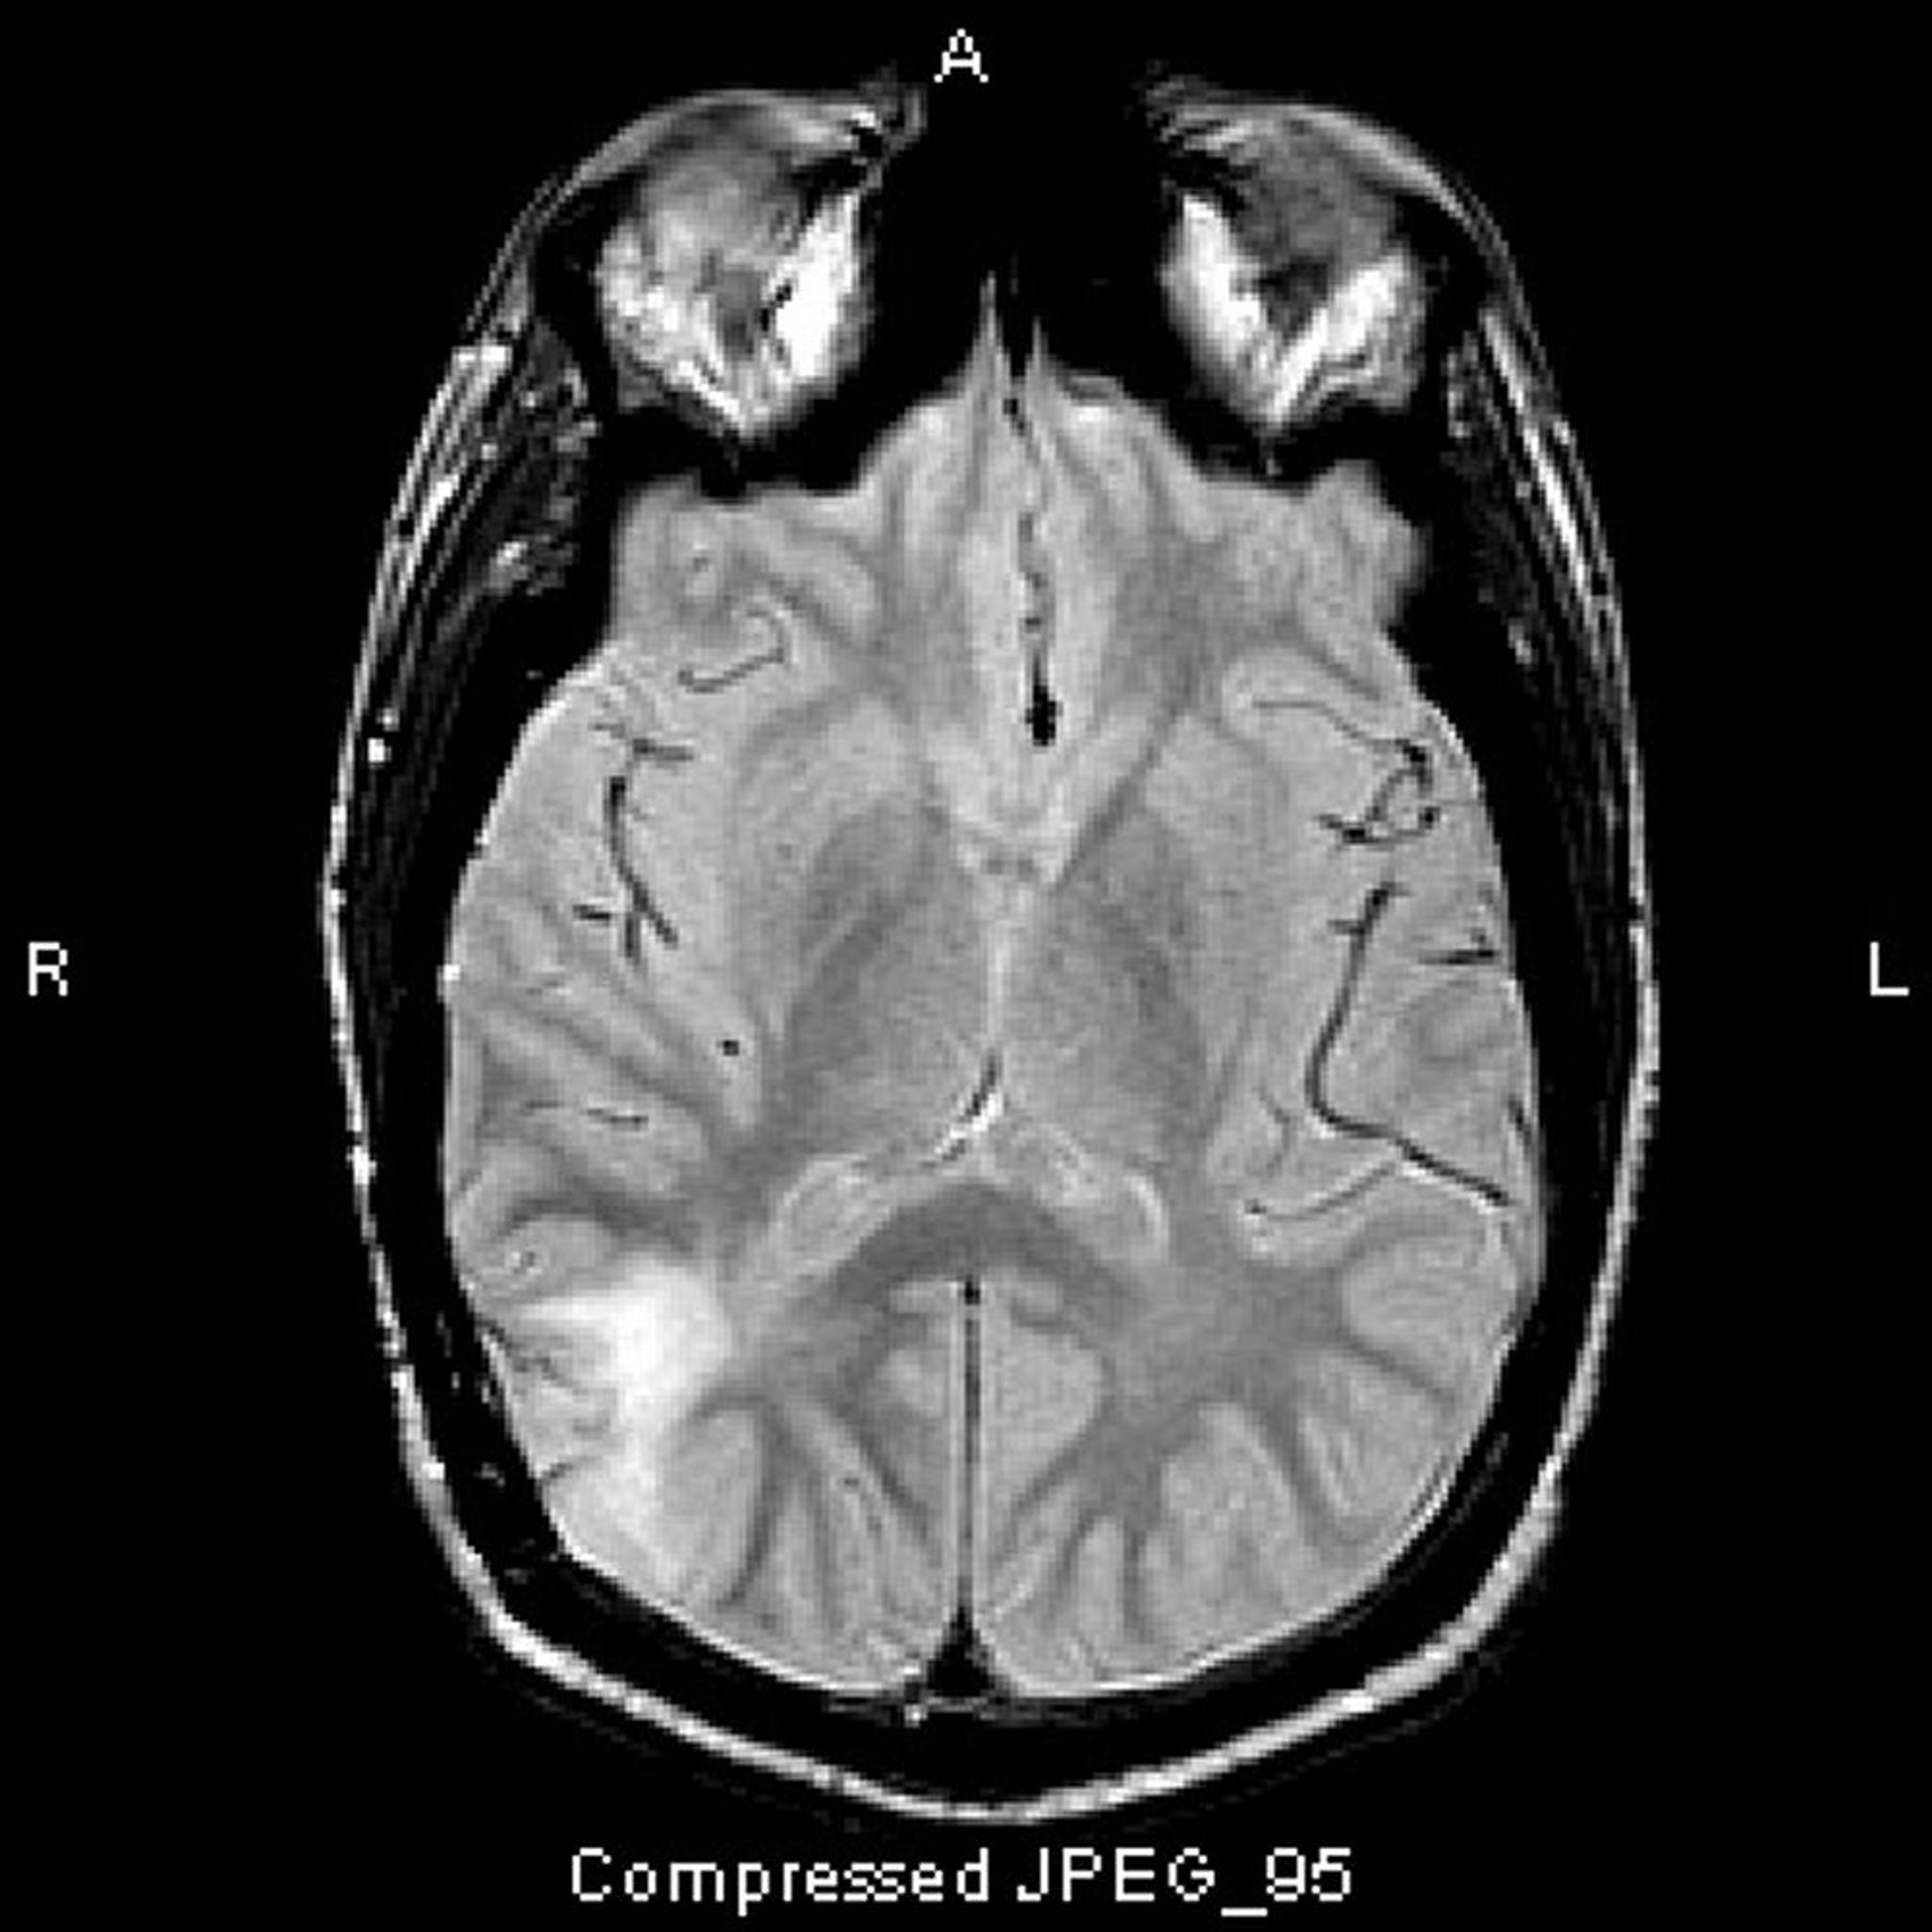

Анапластическая астроцитома

На этом МРТ-скане, выполненном в режиме T2-FLAIR, показан гиперинтенсивный сигнал в заднем отделе височной доли. Сигнал не усиливается при контрастировании. Это анапластическая астроцитома (III степени)

Image courtesy of William R. Shapiro, MD.